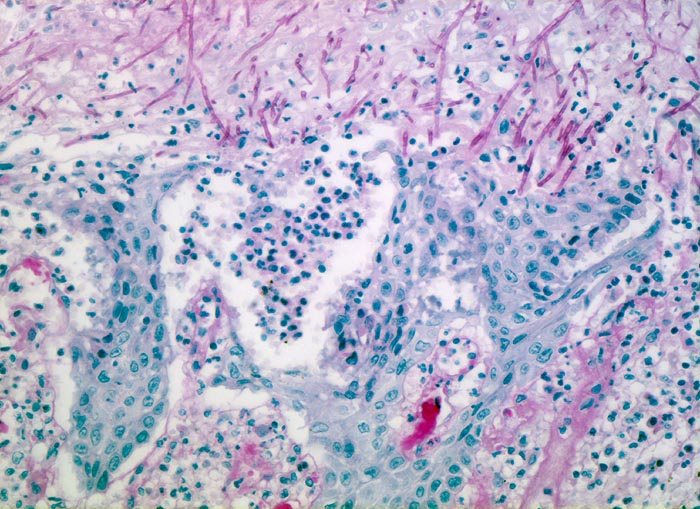

Endoskopisch finden sich abstreifbare weissgelbe krümelige Plaques, welche keine Prädilektionsstelle zeigen. Die Schleimhaut kann erodiert oder ulzeriert sein. In Klumpen von nekrotischen Plattenepithelzellen lassen sich mikroskopisch oft Sporen und Pseudohyphen nachweisen. Die Pseudohyphen wachsen oft senkrecht zur Epitheloberfläche. Besonders gut sichtbar werden die Pilze in der PAS oder Grocott Färbung. Zusätzlich besteht eine aktive Ösophagitis mit Infiltration der oberflächlichen Plattenepithelschicht durch neutrophile Granulozyten. Zahlreiche neutrophile Granulozyten in einem Ulkus weisen auf eine Soorösophagitis. Bei viral bedingten Ulzera (Herpes, CMV) prädominieren Makrophagen.

• Die Pseudomembran über der ulzerierten Schleimhaut setzt sich zusammen aus einem dichten Netzwerk PAS positiver Soorpseudohyphen und ovale aussprossende Sporen, nekrotischem Plattenepithel, Fibrin und neutrophilen Granulozyten.

• Im Unterschied zur Aspergillose dünnere Pseudohyphen ohne echte Verzweigungen und zahlreiche Sporen.

• Verdacht auf Soorinfektion (Pilze besser nachweisbar in der PAS oder Grocottfärbung als in der routinemässig angefertigten HE Färbung).